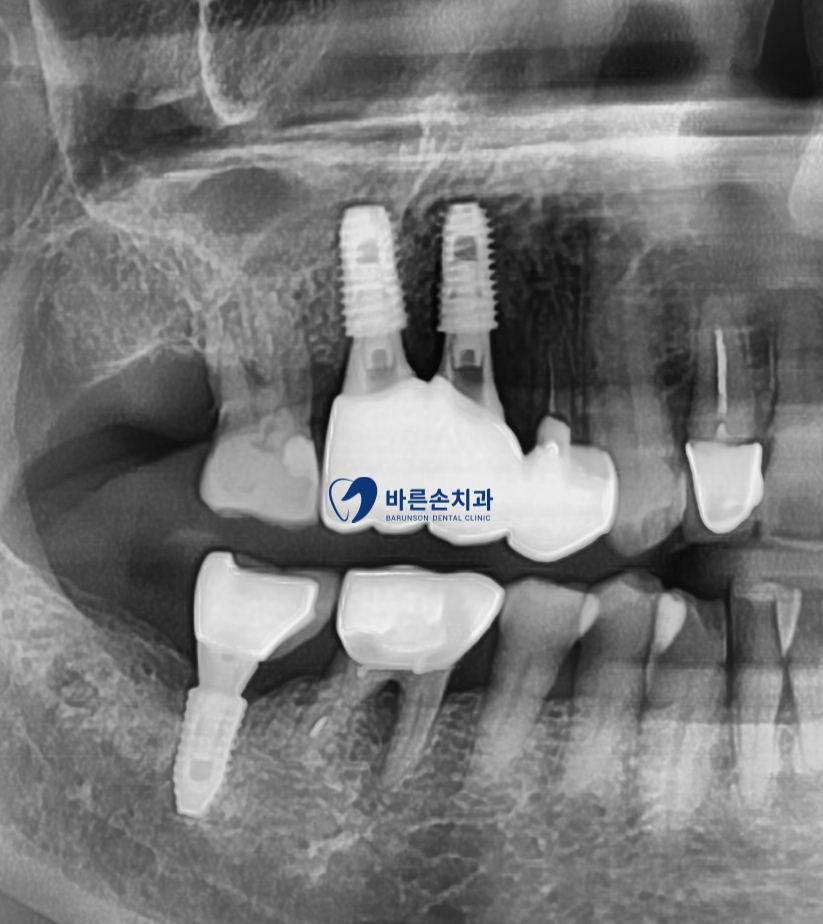

통증의 원인된 치아 발치와 함께 기존에 있던 염증을 깨끗히 제거 합니다

염증으로 인해 치조골 손상도가 높은 케이스라 상악동 거상과 치조골 이식을 동반하였습니다

이로 인해 알맞은 위치에 임플란트가 잘 고정되어져있는게 보이네요^^

이 후 임플란트가 환자분 치조골에 잘 결합되도록 약 3개월의 기다림이 필요합니다